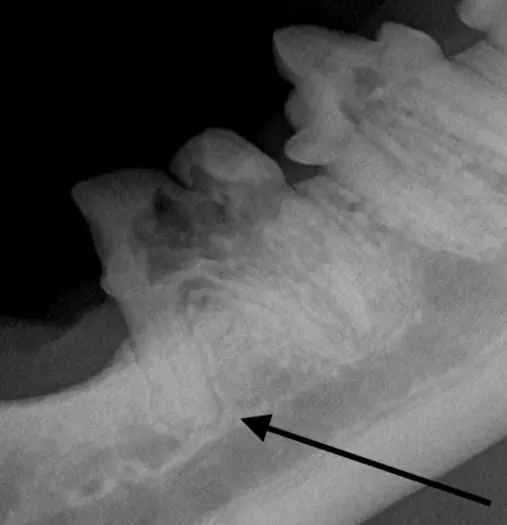

Root ankylosis, root resorption, root dilaceration (ie, curvature), and/or bulbous roots can increase the difficulty of a tooth extraction (Figure 12). Tooth roots occasionally break during extraction attempts. Diseased tooth roots should typically not be left in place due to the potential for pain and infection.5 Safe root extraction includes removal of additional alveolar bone or widening of the alveolus with a high-speed bur to create a moat around the remaining root fragment prior to lifting it out (see Suggested Reading).5

Root ankylosis (A), root resorption (B), bulbous root (C; arrow), and root dilaceration (ie, curvature) (D; arrow) are tooth root anomalies that can increase the difficulty of tooth extraction.

Root tips may be easily displaced into the mandibular canal or the nasal passage and maxillary sinus. Displacement is more likely with significant oral disease or bone loss around the root apex. Roots displaced into abnormal locations should be removed surgically by a board-certified veterinary dentist.